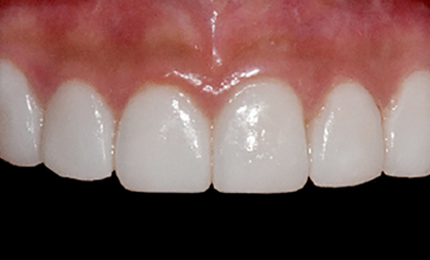

• 재 시술전

기존 보철물 제거 후 폴리싱

재 시술 후

타치과 무삭제라미네이트 후 불만족으로 인한 재시술 케이스